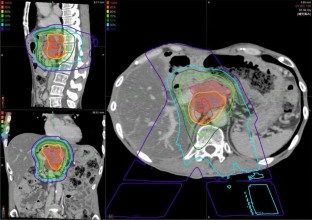

We report a case of a male in his 50 s who underwent pancreaticoduodenectomy for solid pseudopapillary neoplasm (SPN) of the pancreas at 30 years. He developed a liver abscess 15 years after the surgery, and CT scan revealed a swollen retroperitoneum lymph node and a tumor in the liver. Symptoms, including abdominal distension, appetite loss, and epigastric pain, appeared due to lymph node metastasis. Endoscopic ultrasonography-guided fine-needle aspiration against the lymph node revealed SPN recurrence. The tumor had invaded the common hepatic artery, and surgery was not indicated. Chemotherapy of Gemcitabine/nab-Paclitaxel biweekly was performed 8 times; however, no reduction in tumor size was observed, and the patient’s symptoms worsened. Proton beam therapy (67.5 GyE in 25 fractions) was subsequently performed for lymph node metastasis, and led to a gradual reduction in lymph node metastasis, and an improvement in symptoms. No re-expansion of lymph node metastasis has been observed 3 years after proton beam therapy. Since SPN is low malignancy and most cases can be expected to be cured by surgery, there is currently no standard treatment of unresectable SPN. This case is the first report of proton beam therapy for SPN, and was considered to be effective.

Fig. 4

The authors would like to thank Araya Masayuki, Chief Doctor of Aizawa Proton Therapy Center for the implementation of proton beam therapy and the provision of the proton dose distribution map. The authors also would like to thank Enago (www.enago.jp) for the English language review.